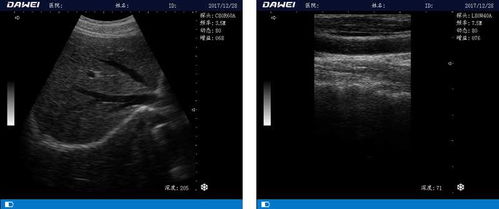

随着计算机技术的不断发展,DOS系统B超经历了从黑白到彩色、从二维到三维的演变。这一时期,DOS系统B超在临床诊断中发挥着重要作用,为医生提供了丰富的影像信息。

3. 功能丰富:DOS系统B超具备丰富的功能,如二维图像、多普勒血流成像等,满足临床诊断需求。

1. 图像质量有限:与当前先进的医学影像技术相比,DOS系统B超的图像质量存在一定差距。